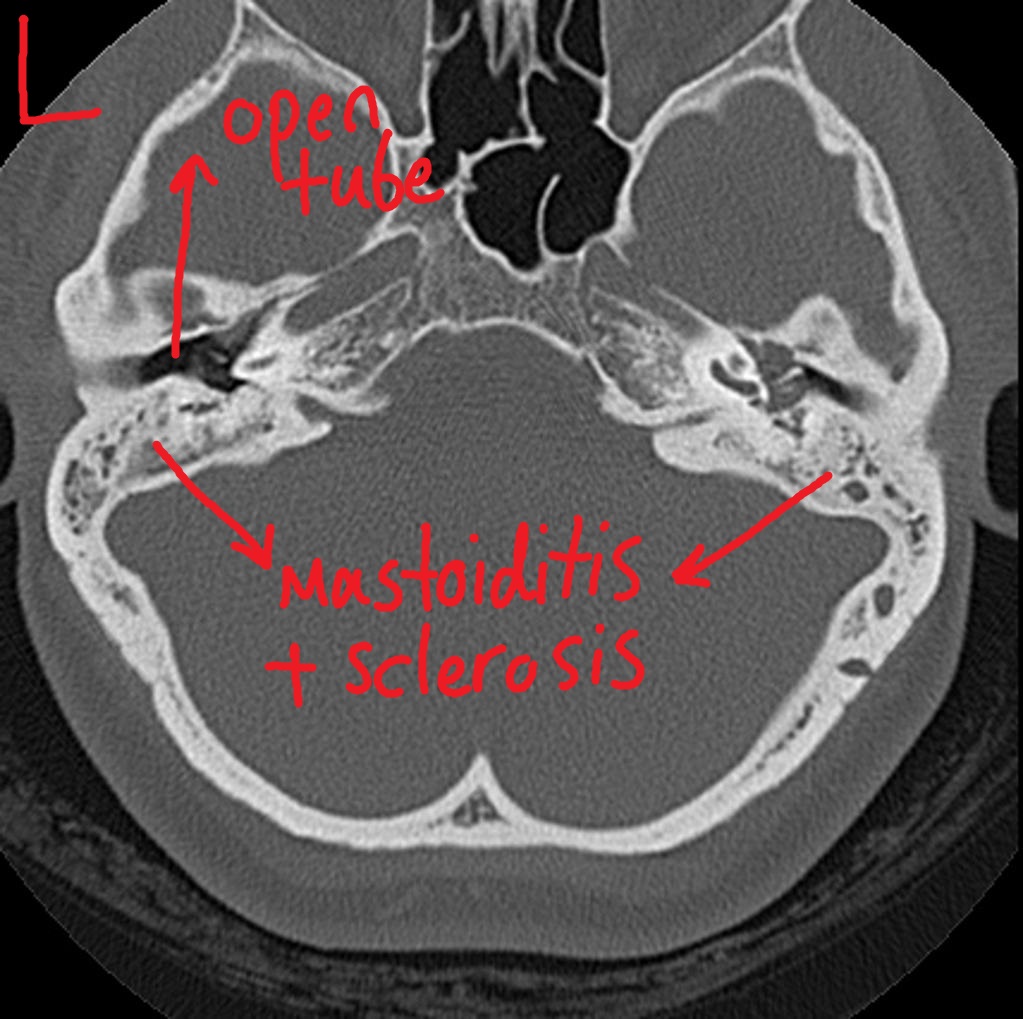

Sinusitis/Mastoiditis Undergraduate Diagnostic Imaging Fundamentals Mastoid Lump Behind Ear A bump behind the right ear could develop due to many reasons, including acne, a cyst, a swollen lymph node, or mastoiditis. Mastoiditis is an infection of your mastoid process, or the large bone behind your ear. Mastoiditis is a serious infection of the mastoid, the hard, prominent bone just behind and under the ear. This infection develops in the. Mastoid Lump Behind Ear.

Mastoiditis CT wikidoc Mastoid Lump Behind Ear In turn, you may feel those as lumps or knots. Mastoiditis, for example, is a bacterial infection of the mastoid bone behind the ear. Mastoiditis is an infection of your mastoid process, or the large bone behind your ear. The unidentified lump you're feeling behind your ear is most likely within the outer ear or the skin surrounding it. This. Mastoid Lump Behind Ear.

Mastoiditis CT wikidoc Mastoid Lump Behind Ear The mastoid bone, a component of the skull that's close to the ear, can also. A bump behind the right ear could develop due to many reasons, including acne, a cyst, a swollen lymph node, or mastoiditis. This condition usually results from an untreated middle ear infection and symptoms. Mastoiditis is an infection of your mastoid process, or the large. Mastoid Lump Behind Ear.